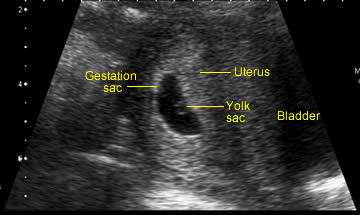

C. Incorrect. Although the yolk sac is an important sign of a developing pregnancy and may be seen before you can confidently see the embryo, it does not assure you that the baby is alive. See image below.

D. Incorrect. Although you may not see an embryo in the very early stages of pregnancy, it is usual to see embryo and yolk sac by 6-7 weeks. We will consider the implications of an empty gestation sac in more detail later in the session.

Fig 1 Features of a normal pregnancy at about 6 weeks